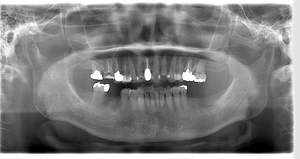

インプラント治療の症例4

レントゲン写真

- Befor

- After

口腔内写真

| 年齢 | 50代・男性 |

|---|---|

| 主訴 | 部位:左下6番7番 主訴:左下奥歯腫れて痛い。 |

| 治療内容 | 左下6番抜歯、左下6番7番骨造成、インプラント埋入 |

| 治療費 | 合計:1,232,000円 ・内訳 診断料:55,000円 サージカルガイド2本:66,000円 GBR:110,000円×2本 埋入料:165,000円×2本 静脈内鎮静麻酔:77,000円 2次OPE:22,000円×2本 仮歯:55,000円×2本 上部構造(フルジルコニア):165,000円×2本 (2023年1月現在) |

| 治療期間 | 約8ヶ月 |

| リスク・副作用 | リスク・副作用 |

| 治療方針 | 元々支台歯に負荷がかかりやすいとされている延長ブリッジを抜歯し、1本単体でしっかりかめるようにインプラントを2本埋入した。骨吸収も進んでいたため、※GBR法で骨造成を同時に行った。 治療と並行して、全顎的な歯周病治療も行い、今後は歯周病が進行しないよう、こまめにメンテナンスに通っていただく。 |

| 特記事項 | ※1 GBR・・・骨再生誘導法。骨の高さや厚みを人工骨や人工膜などを使用し再生する方法 |

| 担当者所見 | 6番は歯根分割された被せ物が7番の欠損部との延長ブリッジとされており、強い咬合と歯周病も相まって負荷がかかり動揺し、歯として機能しなくなったため、抜歯となった。 |